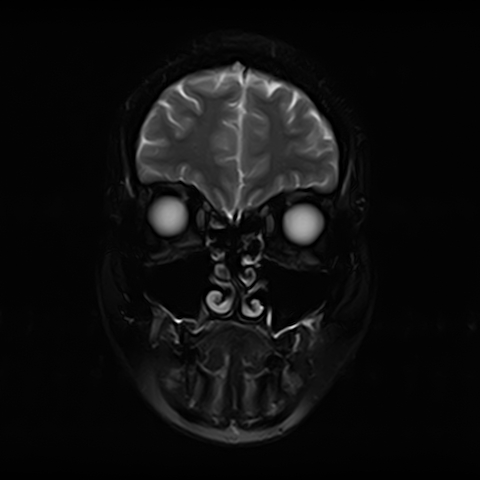

Височно-нижнечелюстной сустав является парным комбинированным суставом и имеет сложное строение. В него входят суставные ямки височной кости, суставные головки нижней челюсти и расположенные между ними хрящевые пластинки – мениски, выполняющие роль амортизаторов.

Чаще всего дисфункция височно-нижнечелюстного сустава обусловлена внутренним повреждением, смещением мениска и суставной головки нижней челюсти. Для определения степени смещения внутрисуставных структур выполняется функциональная проба с проведением МРТ в двух положениях:

Магнитно-резонансная томография является наиболее точным и эффективным методом диагностики поражения височно-нижнечелюстных суставов, так как позволяет получить детальную информацию о состоянии не только костей, но и связочного аппарата, хрящей, менисков, жевательных мышц, окружающих мягких тканей.

При проведении магнитно-резонансной томографии на изображениях визуализируются: височная кость, головка мыщелкового отростка нижней челюсти, суставная щель. Помимо костных структур МРТ позволяет оценить состояние мягких тканей – внутрисуставного диска и связочного аппарата височно-нижнечелюстного сустава, жевательных мышц.

МРТ ВНЧС с капой включает в себя два протокола: с открытым ртом и с закрытым ртом. Данная функциональная проба позволяет проследить степень смещения внутрисуставных анатомических структур и оценить биомеханику движений в суставе.